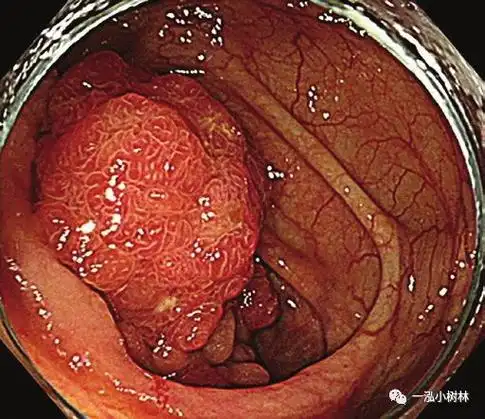

贵阳微创胃肠专科医院: 胃息肉,到底要不要斩草除根?_癌变_直径_cm

什么样的胃肠息肉才要割掉?